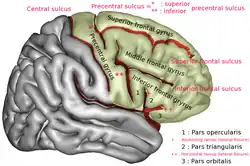

Middle frontal gyrus of the human brain. | |

The borders of the middle frontal gyrus are the inferior frontal sulcus below; the superior frontal sulcus above; and the precentral sulcus behind.[1]

Position of middle frontal gyrus (shown in red).

Lateral surface of left cerebral hemisphere. Lateral surface of right cerebral hemisphere. Middle frontal gyrus is noted by red arrows.